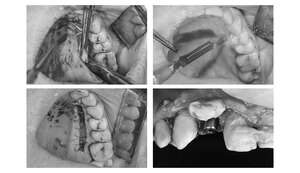

【担当医師所見】

歯ぐきを切ってインプラントを埋入しました。埋入後は歯ぐきを縫って終わります。

この状態で4ヶ月待ちインプラントと骨の生着を待ちます。